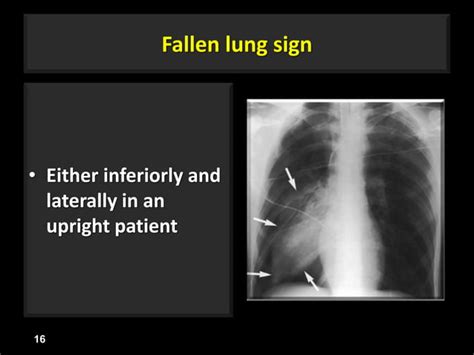

SlideShare

Deep sulcus sign fallen lung sign-ct angiogram sign-flat-waist sign

638×478

slideshare.net

Deep sulcus sign fallen lung sign-ct angiogram sign-flat-waist sign | PPTX | Lung and ...